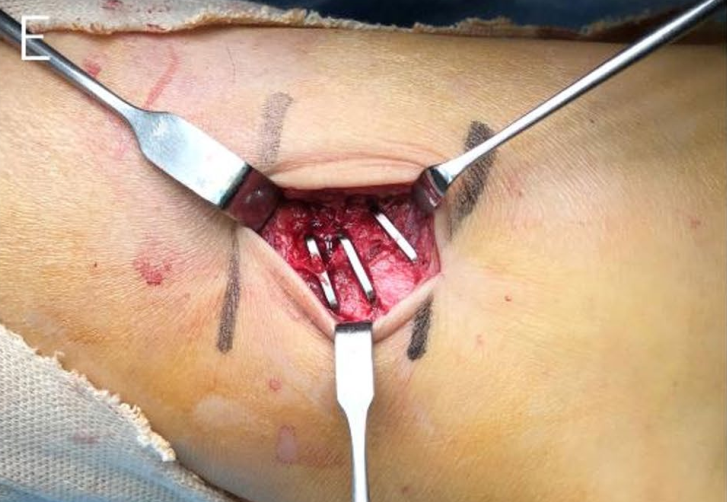

与肱骨干骨折相似,在桡骨干横行骨折的固定中,也可采用骑缝钉临时固定后,再通过钢板螺钉系统确切固定:

【3】Song EY, Emovon EO 3rd, Hollins AW, Saltzman EB, Mithani SK, Richard MJ, Pidgeon TS. The Use of Nitinol Staples as Reduction Aids in Fixation of Forearm Diaphyseal Fractures: Surgical Technique and Case Series. Tech Hand Up Extrem Surg. 2025 Mar 1;29(1):e0496.